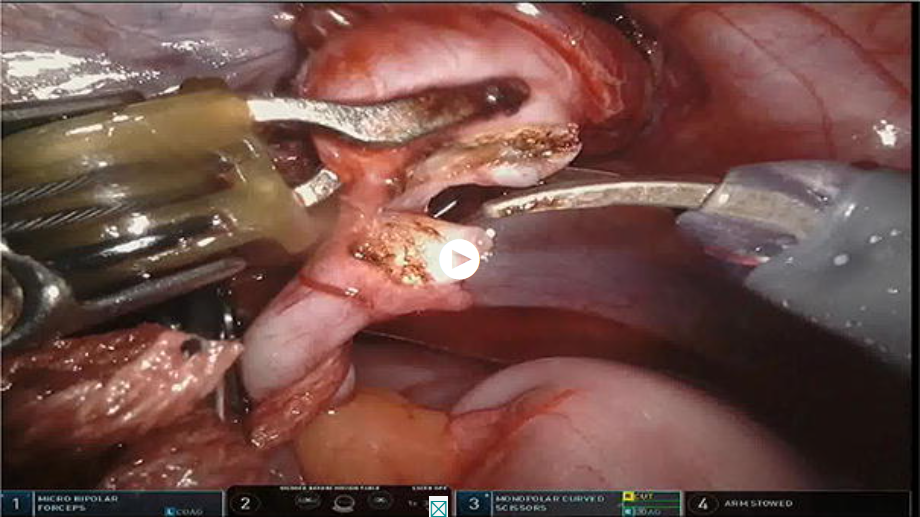

Bilateral Robot-Assisted Laparoscopic Dismembered Extravesical Cross-Trigonal Ureteral Reimplantation with Tailoring for Vesicoureteral Reflux and Primary Obstructive Megaureter (BI-RADECUR)

Leon Chertin, Amnon Zisman, Jaudat Jaber, Boris Chertin, and Stanislav Kocherov

View Video